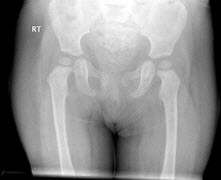

181、单项选择题

女,根据其正常骨盆影像图像,判断其最可能的年龄()

A.1岁左右

B.5岁左右

C.3岁左右

D.7岁左右

E.9岁左右